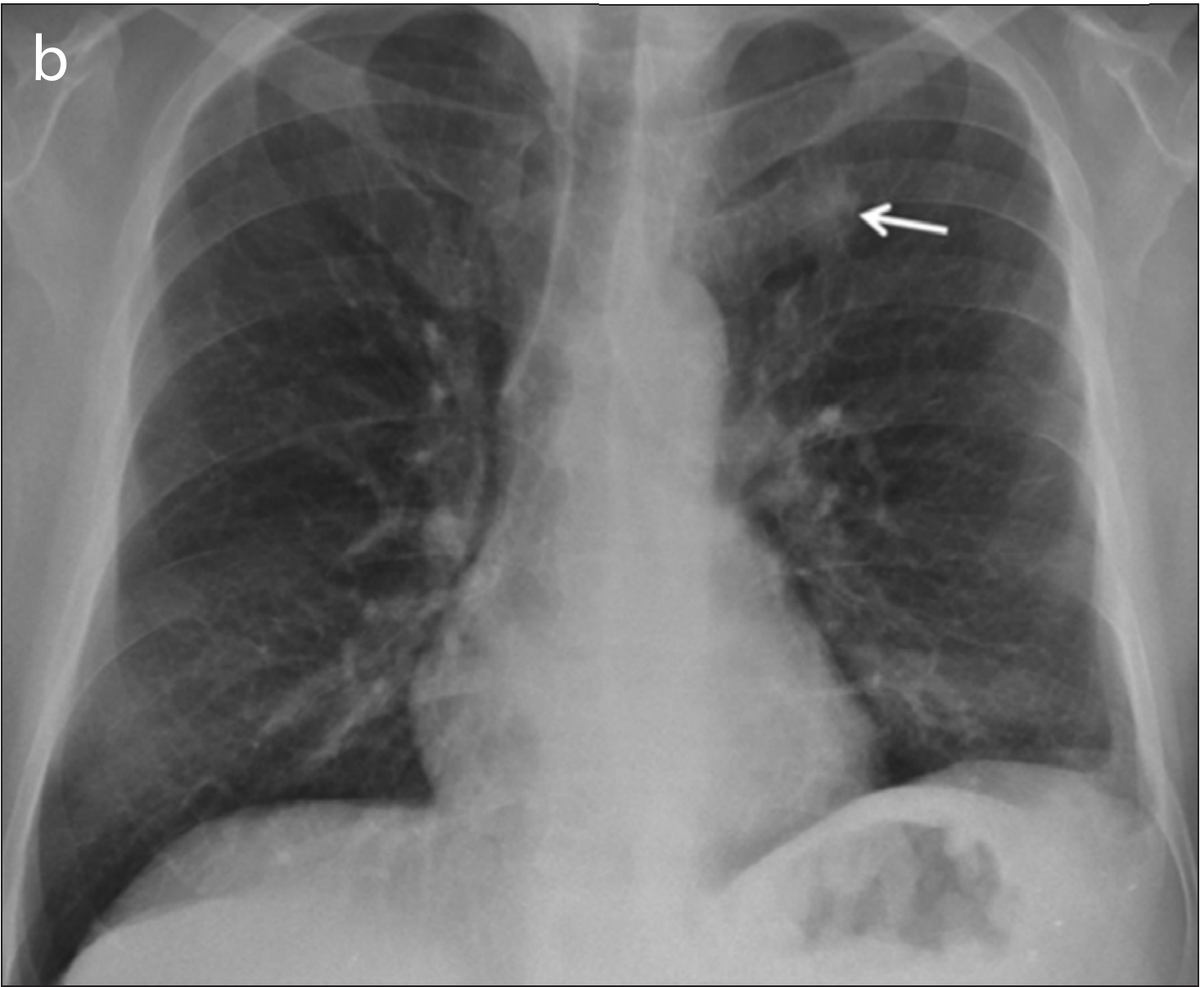

The images in the panels below highlight some of these difficulties. Example 1 shows the chest X-ray of a 62-year-old man with a tumor located in his upper right lung. The tumor is partially obscured by the collar bone and is difficult to see. When analyzed by a group of twelve radiologists, three members of the panel missed the tumor as part of their review. Though they recognized the presence of the tumor during a second review (more detail about that below).

Example 1: 62 year old man with adenocarcinoma

The second image in example 1 (taken from the 2019 Sim paper) highlights how Deep Learning models can help radiologists focus on a region of concern by providing an AI-generated annotation. While three of the twelve radiologist reviewers missed the tumor without the annotation present, all twelve reviewers were able to identify its presence with AI assistance.